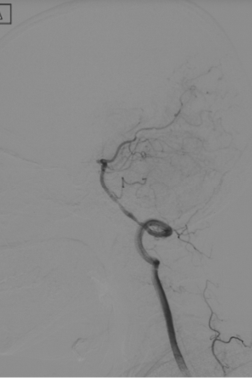

R-CA

波科支架怎么样径技-弓上病例大赏|第210期·右侧颈内动脉球囊扩张术+支架植入术_https://www.jmylbn.com_新闻资讯_第12张

VA

波科支架怎么样径技-弓上病例大赏|第210期·右侧颈内动脉球囊扩张术+支架植入术_https://www.jmylbn.com_新闻资讯_第13张